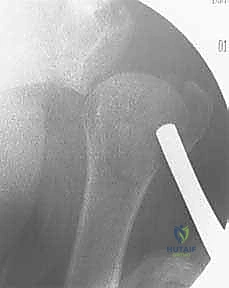

4. إدخال الأسلاك المعدنية (K-wires)

بمجرد أن يصبح الكسر في الوضع المثالي، يتم إدخال أسلاك كيرشنر (Kirschner wires) الدقيقة عبر الجلد مباشرة إلى العظم. يتم توجيه هذه الأسلاك بزوايا هندسية مدروسة لضمان أقصى درجات الثبات. عادة ما يتم استخدام 2 إلى 4 أسلاك.

5. التحقق من الثبات وقص الأسلاك

بعد وضع الأسلاك، يتم تحريك الكتف بحذر للتأكد من ثبات الكسر التام. بعد ذلك، تُقص نهايات الأسلاك وتُترك بارزة قليلاً فوق الجلد (أو تُدفن تحت الجلد مباشرة) لتسهيل إزالتها لاحقاً.

6. التقييم النهائي والإغلاق

تُؤخذ صور شعاعية نهائية لتوثيق نجاح العملية، وتُغطى مواقع دخول الأسلاك بضمادات معقمة.